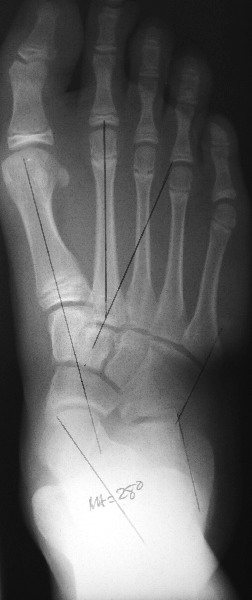

Pertinent Points On Diagnostic Imaging

Assess standard weightbearing views (AP, lateral and oblique views of the foot and ankle) for degenerative changes and angular deformity. Evaluating ankle films helps in ruling out a valgus deformity within the ankle joint. One can measure the talo-first metatarsal angle on AP and lateral foot radiographs. Obtaining a hindfoot alignment view and long leg calcaneal axial views can help in determining the level of valgus deformity (STJ vs. AJ vs. calcaneus). When assessing adolescent patients, clinicians should rule out tarsal coalitions. Obtaining a MRI can be helpful to rule out fibrous or cartilaginous coalitions in these patients. Advanced imaging is also beneficial to evaluate joint integrity when deciding between joint sparing procedures or an arthrodesis.